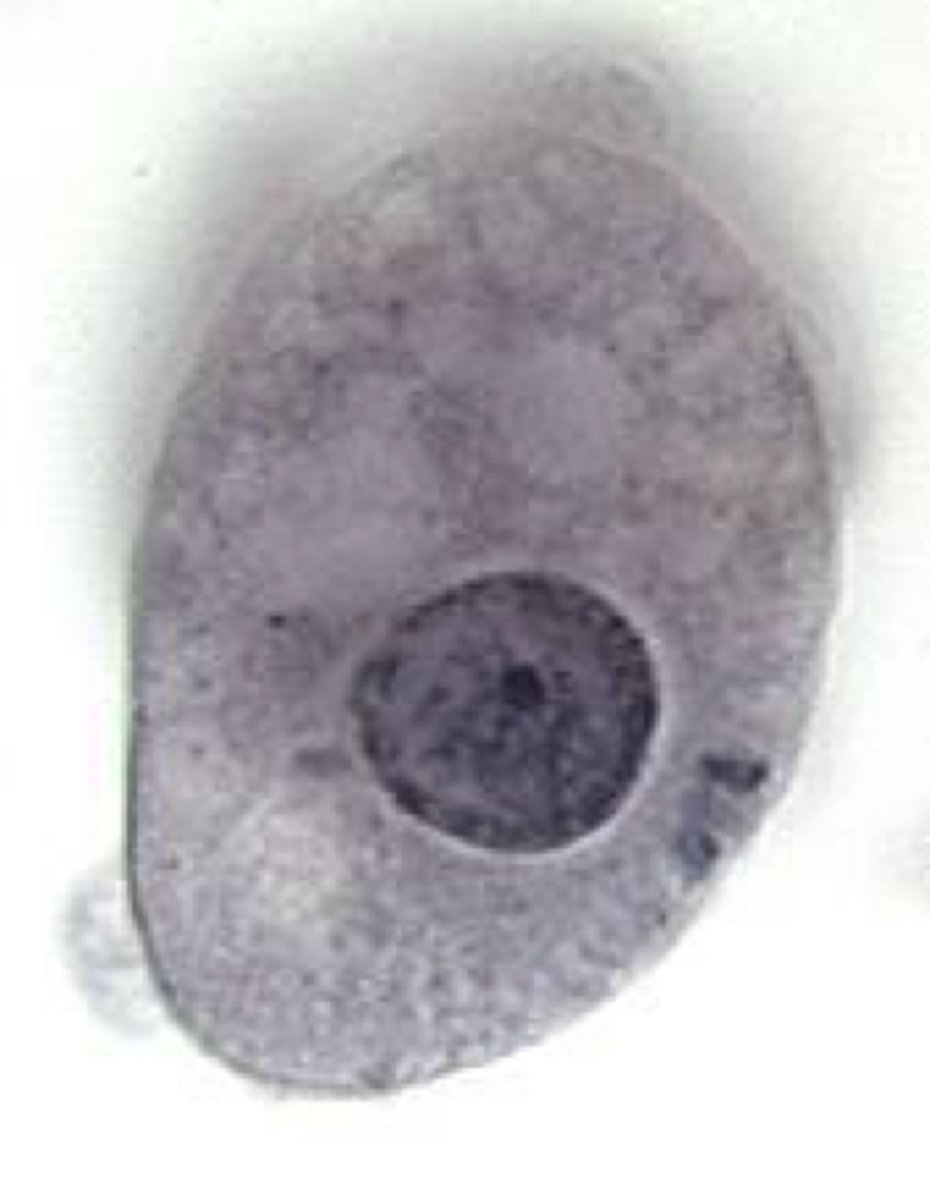

Leishmania donovani - Amastigote

Name the stage and species

<p>Name the stage and species</p>